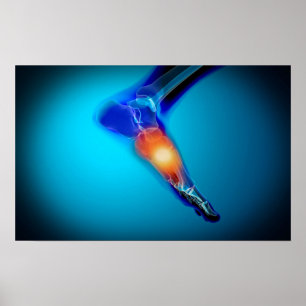

Toile Image Conceptuelle De La Douleur Dans Le Pied Huma

Prix242.00 CHF